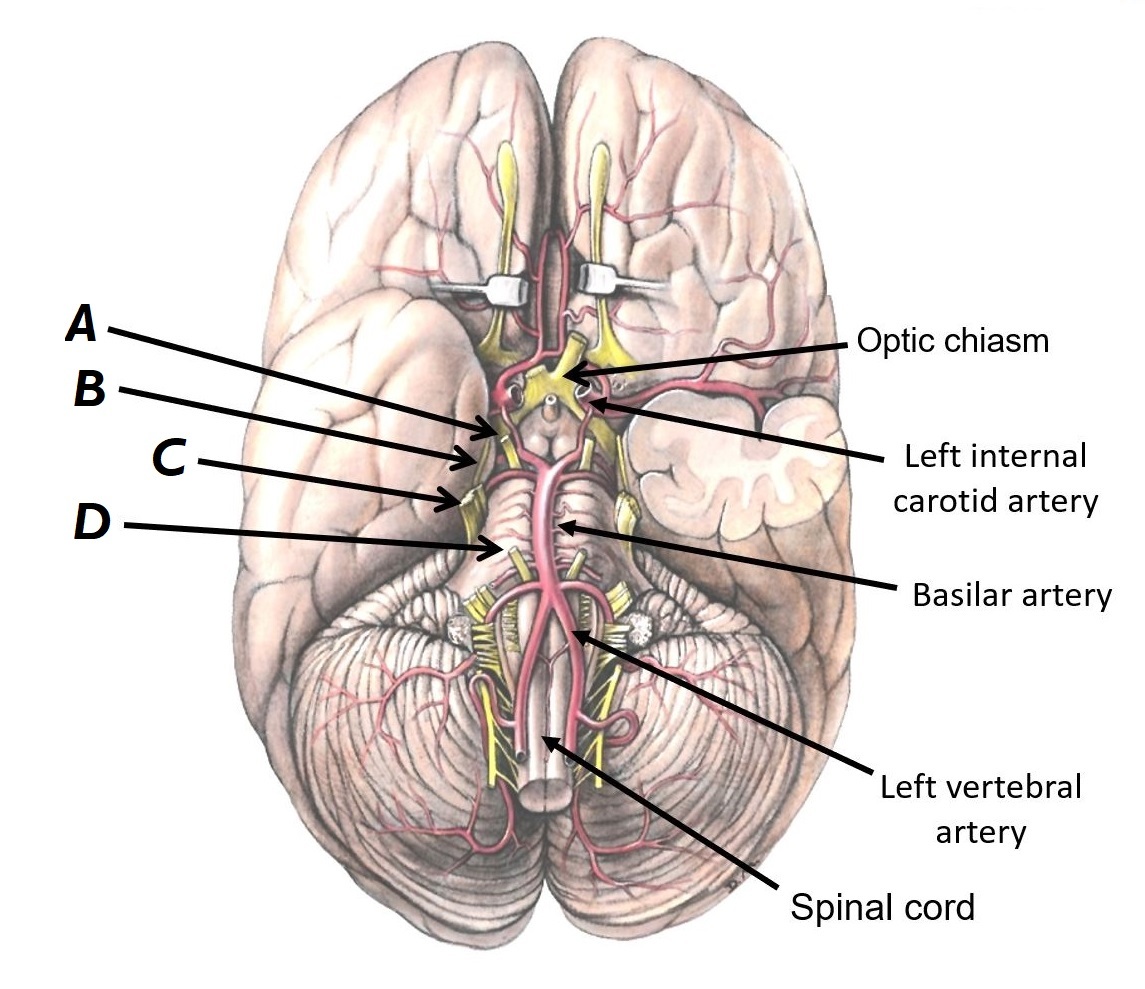

Name structures A to D

A - Optic chiasm

B - Left internal carotid artery

C - Basilar artery

D - Left vertebral artery